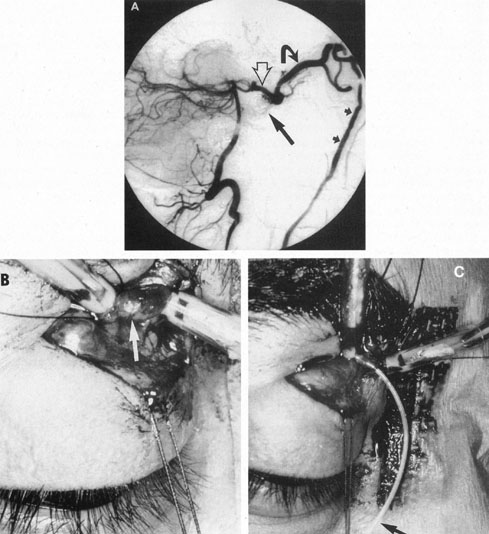

Therapy for carotid–cavernous fistula is directed toward relieving ocular symptoms, especially where visual loss is threatened, with the goal being thrombosis of the fistula with normalization of orbital hemodynamics. Various arterial ligatures, trapping procedures, controlled embolizations, and even direct intracranial attacks have been advocated, but the current trend indicates the great advance represented by intravascular closure using detachable balloon microcatheterization techniques (Fig. 17).106 Complications of these techniques include transient or fixed hemispheral dysfunction, cranial nerve palsies, field loss, and pseudoaneurysm formation.106,112 At least one case of acute angle-closure glaucoma was reported after transvenous embolization of a traumatic carotid–cavernous fistula necessitating emergency laser iridotomy.113 The complication was thought to arise from oculomotor palsy related to the coil pack within the ipsilateral cavernous sinus. However, complication rates are apparently low. In a series of 100 consecutive patients treated for direct carotid–cavernous fistula with detachable balloons, Lewis et al 114 reported an approximately 4% overall complication rate. Endovascular treatment of dural (indirect) carotid–cavernous fistulae is usually directed transvenously also using fibered platinum coils or, less often, liquid adhesive. A recent retrospective evaluation of 135 consecutive patients treated for dural carotidcavernous fistulae over a 15 year period by Meyers et al115 revealed low permanent morbidity of 2.3% and high 90% rate of clinical cure.

Fig. 17. A 32-year-old woman was accidentally shot in the right eye with a low-velocity missile. The initial recovery was excellent, except for loss of the right eye. Five days after the injury, left proptosis and bruit developed. Two weeks after the injury, she developed paralysis of the left sixth and fourth nerves, and visual acuity decreased to 20/400 (6/120) in her remaining (left) eye. An interventional neuroradiologic procedure was performed with complete return of function in the left eye. A: Left carotid arteriogram with immediate opacification of entire cavernous sinus (arrows). B: One-half second after (A) there was extensive filling of dural venous channels and orbital veins. C: Detachable flow-guided balloon (arrows) placed in the fistula under fluoroscopic control and opacified with contrast medium. D: Follow-up left carotid arteriogram after balloon (arrows) placement. The fistula was completely closed with preservation of carotid flow. (Courtesy of Dr. Charles Kerber.)